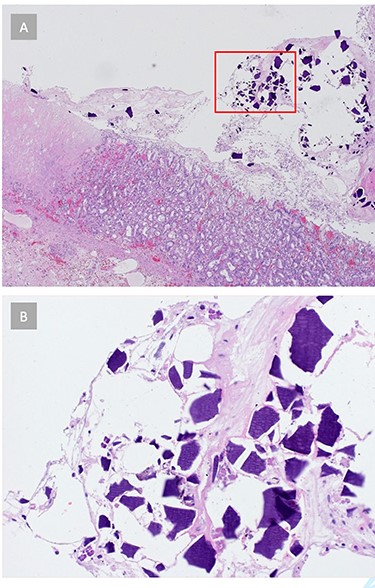

Histopathology showed a resected stomach with GP and circumscribed ischemic transmural necrosis, accompanied by purulent peritonitis (Fig. 3). Several light basophilic crystals in the necrotic gastric mucosa were detected and interpreted as kayexalate crystals (Fig. 4). There was no evidence of GvHD in the remaining gastric mucosa and no signs of a Helicobacter pylori infection. The resection margins were vital.

(A) Histopathology reveals signs of acute gastritis and ischemic tissue areas. Crystalline structures are found in the gastric tissue. (B) Gastric tissue crystals morphologically consistent with kayexalate crystals, suggesting SPS-related ischemic gastritis